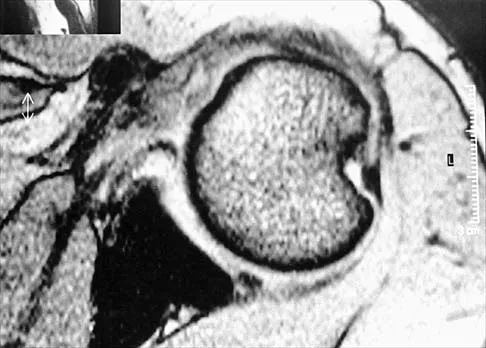

A 25-year-old man has had an insidious onset of left hip pain over the past 11 months. A radiograph, coronal MRI scan, and histopathologic specimens are seen in Figures 2a through 2d. What is the most likely diagnosis?

Explanation

Ewing's sarcoma is the second most common primary sarcoma of bone in children and young adults. It is a malignant round cell tumor with uncertain histogenesis. Sheets of uniform small round blue cells with a high nuclear-to-cytoplasm ratio and the absence of osteoid formation differentiate this histologic diagnosis from the other conditions. Immunohistochemical staining and molecular diagnostic studies are useful to verify the diagnosis.